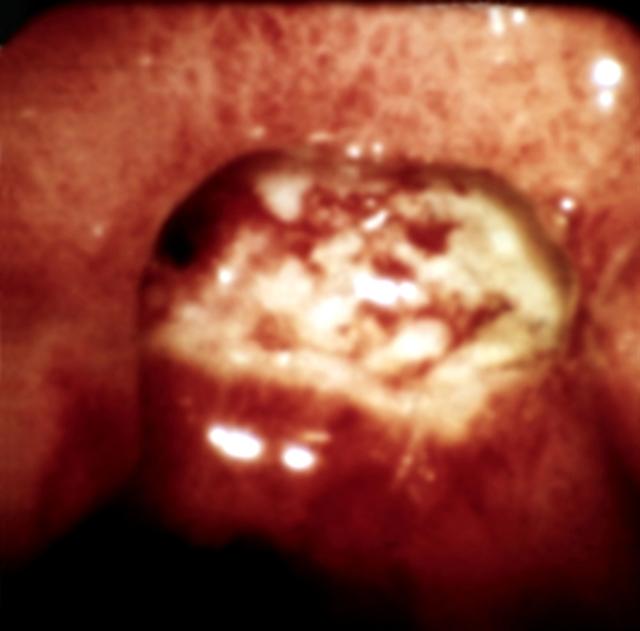

Рис. 7. Эндоскопическая картина желудка в норме и при различных заболеваниях. Язва желудка с пенетрацией в печень: видна глубокая язва с плоским покрытым некротическими массами дном.